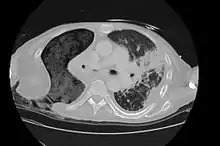

The Eloesser flap is still utilized for patients with chronic empyemas who have not improved despite being treated with antibiotics and first line surgical procedures to remove pus and re-expand the lung such as decortication or video-assisted thoracoscopic surgery.[4] Often they are thought to be too ill for more definitive procedures such as a major thoracotomy or muscle flap transposition.[5] In a recent case series, the most common reasons to need an Eloesser flap were parapneumonic effusions and postresection empyemas, with only 9% done for tuberculosis.[4]